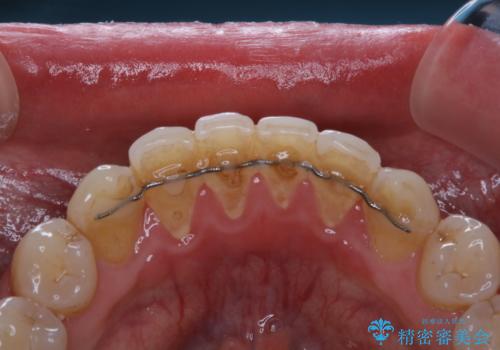

全体的にプラークや歯石が付着していて、歯肉炎が見られました。

状態に合った専門的な器具を使用して、歯質や歯肉へのダメージを抑えながらPMTC(自費クリーニング)60分コースを行いました。矯正治療後の保定装置がワイヤーの場合、フロス・糸ようじが通せないこと、歯ブラシがしずらいことなどにより、歯石プラークなどが付着しやすくなります。そのため専門的な器具による細かいケアを行うことがとても大切です。